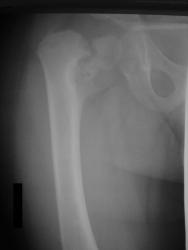

Нет, травмы в данном случае не было. Имеет место дистрофическая coxa vara, вероятнее всего, врождённаяю. Эпифизеолиз головки, который мы видим на снимке, как мы считаем, наступил вследствие нарушений биомеханики в суставе - ШДУ практически 90 градусов. Добавлю, что факт травмы родители категорически отрицают. Ребёнок постепенно начал хромать, хромата усиливалась на протяжении 6 месяцев.

P.s. Сегодня этого ребёнка мы прооперировали.